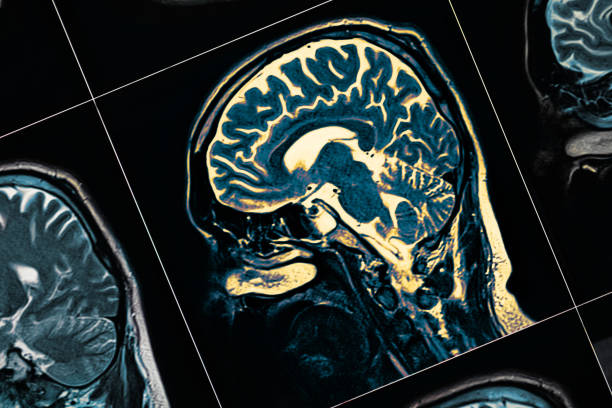

其他專家將參與為您的孩子進行全面的體檢、 血液檢查、心理健康測試、大腦成像測試和其他檢查。它們都是找到正確診斷并制定治療計劃以幫助您的孩子控制疾病的關(guān)鍵。